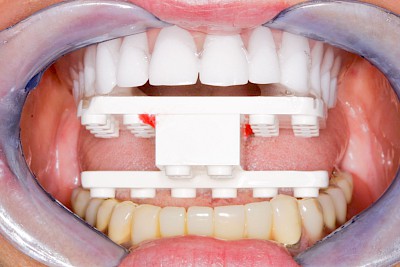

Implantatplanung

Damit Implantate an der richtigen Stelle im Kieferknochen platziert werden könen, gibt es heute vielfältige Möglichkeiten der Planung. In vielen Situationen kann die Erfahrung des Zahnarztes ausreichend sein.

Nicht selten ist jedoch auch eine technisch aufwändigere Vermessung im Vorfeld sinnvoll, z.B.:

- Wenn sich der Kieferknochen abgebaut hat

- Wenn der Nervverlauf im Unterkiefer beachtet werden muss

- Wenn die Ausdehung der Kieferhöhle im Oberkiefer beachtet werden muss

- Wenn wenige Restzähne keine gute Orientierung erlauben

In diesen Fällen kann die Planung mittels verschieden aufwendiger Röntgen-Techniken (Übersichtsaufnahme, DVT) ggf. unter Zuhilfenahme speziell angefertigter Planungsschablonen sinnvoll sein.